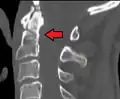

Repair of a dens fracture

A fracture of both pedicles of the axis is termed a Hangman's fracture.

Fractures of the dens are classified into three categories according to the Anderson Alonso system:

• Type I fracture - Extends through the tip of the dens. This type is usually stable.

• Type II fracture - Extends through the base of the dens. It is the most commonly encountered fracture for this region of the axis. This type is unstable and has a high rate of non-union.

• Type III fracture - Extends through the vertebral body of the axis. This type can be stable or unstable and may require surgery.[1]